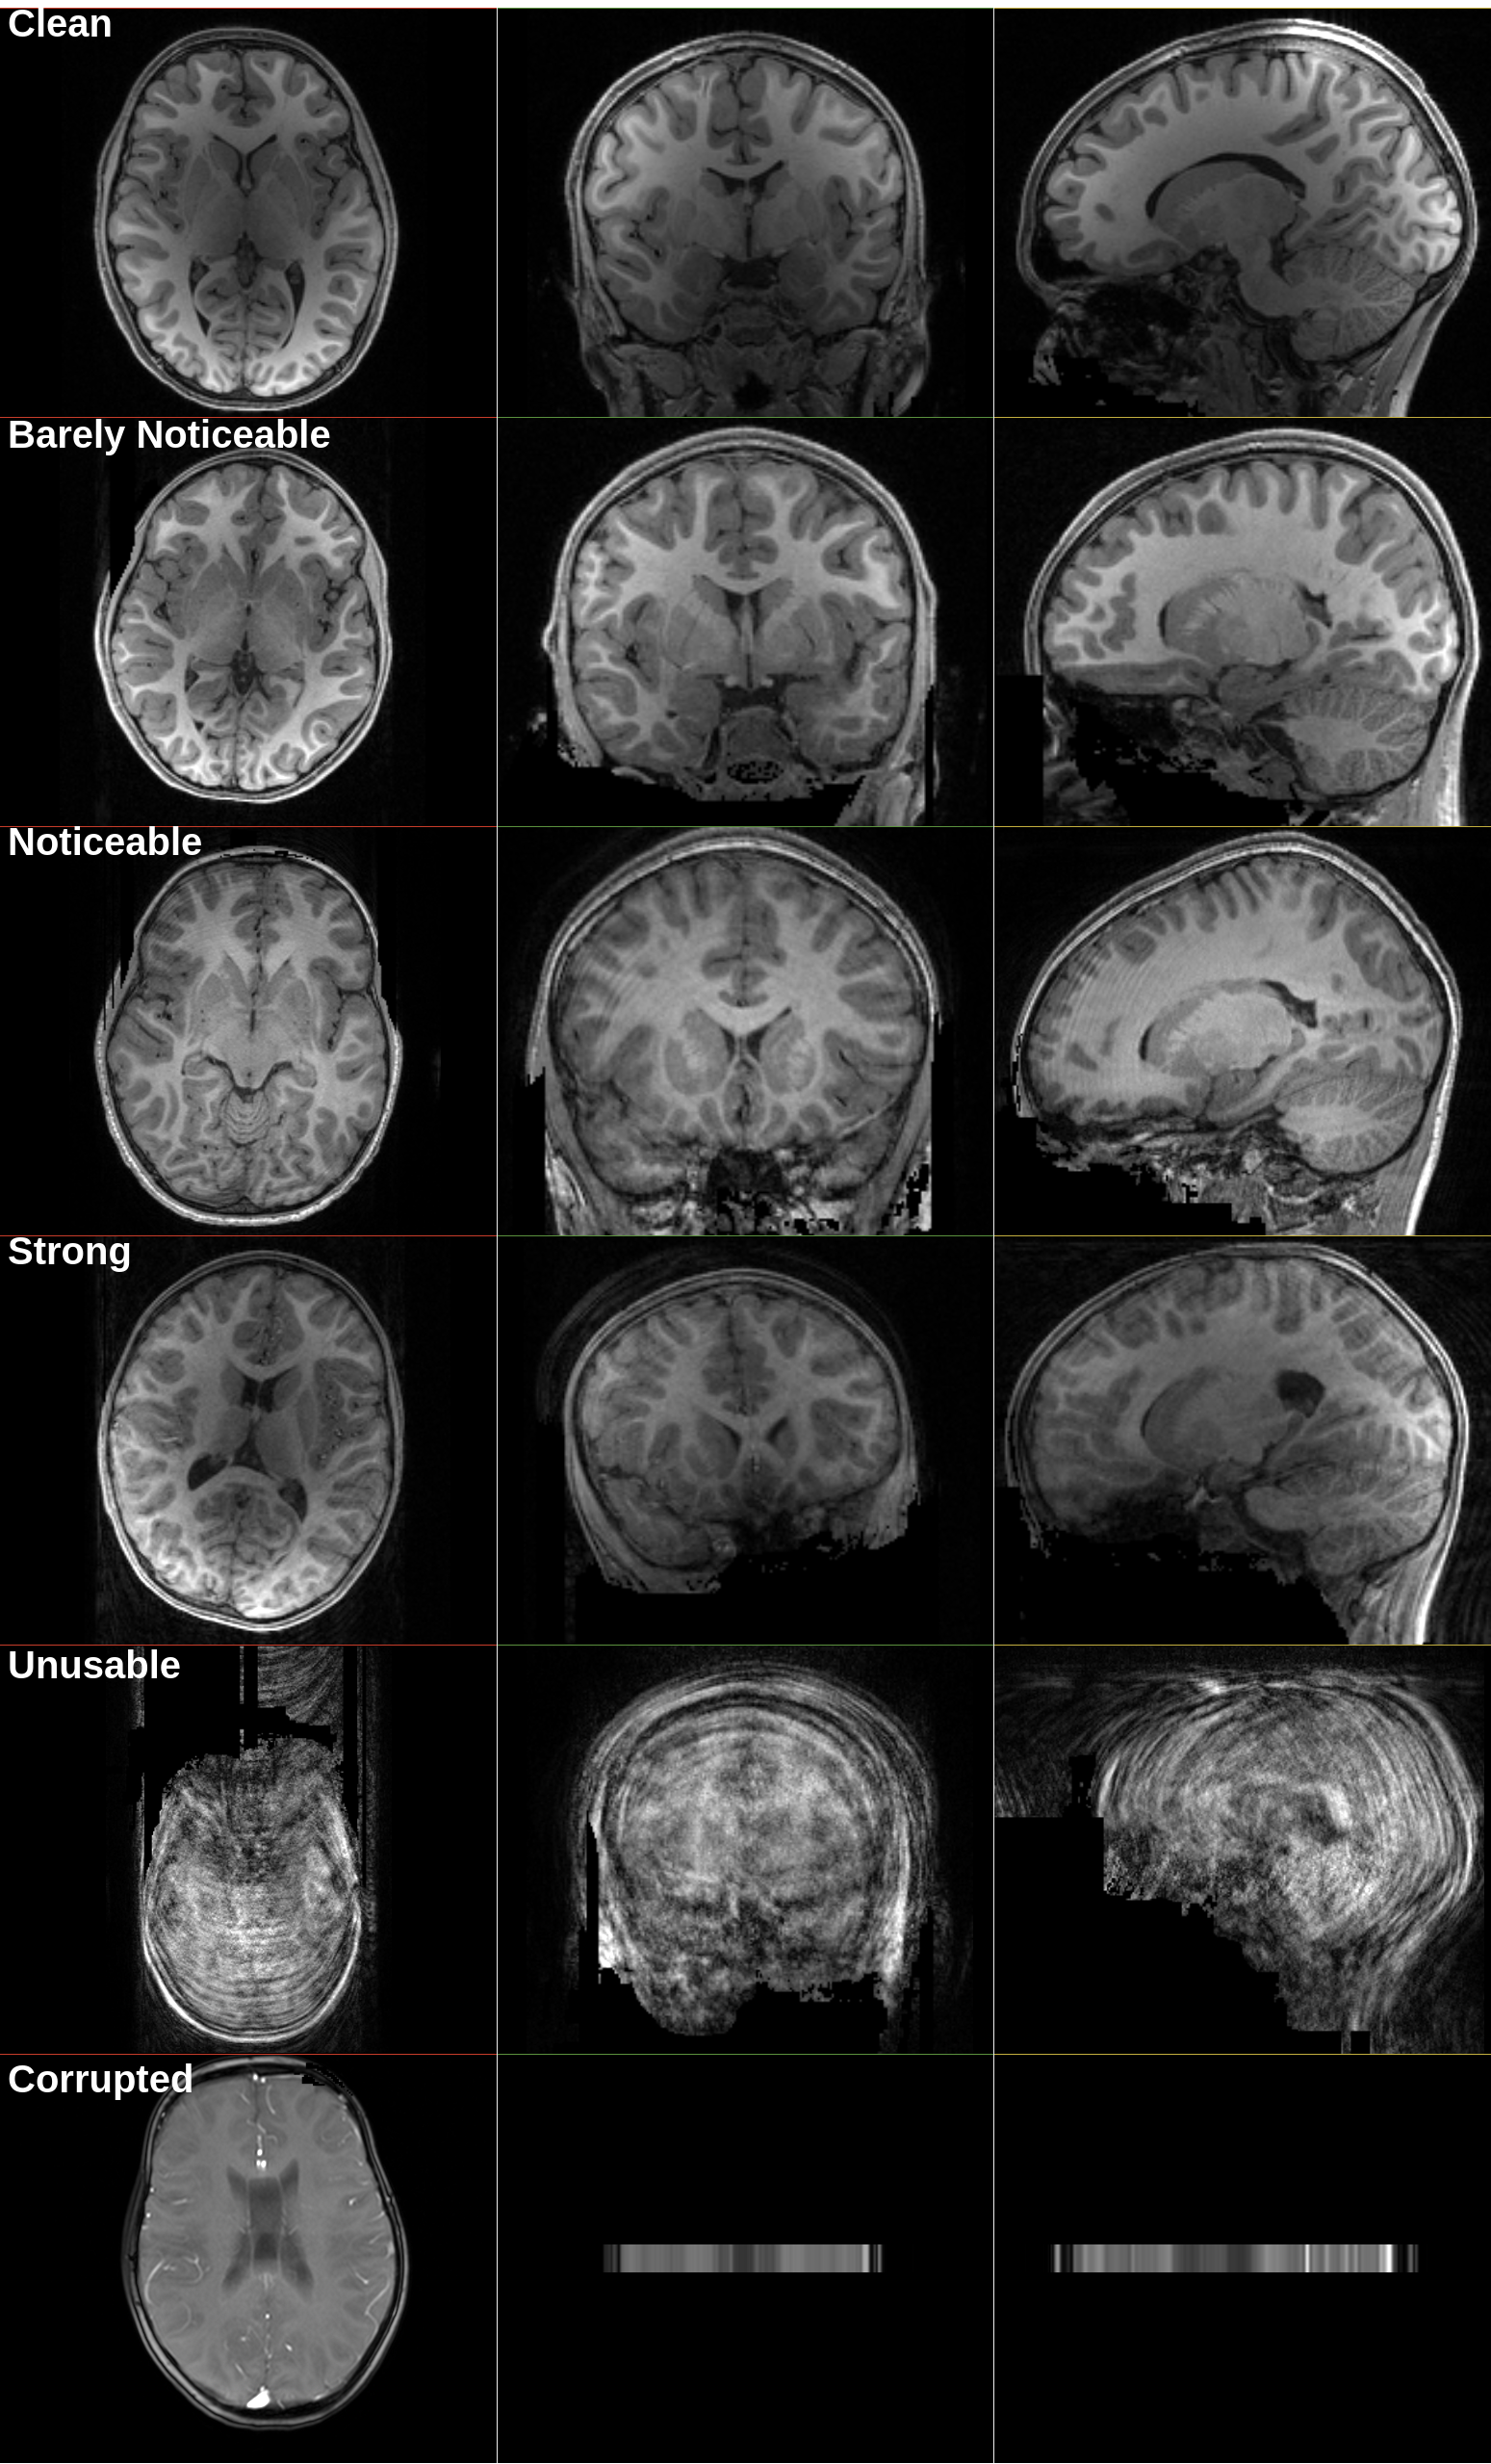

We later improved this rating system with six possible labels: ”Clean”, ”Barely Noticeable”, ”Noticeable”, ”Strong”, ”Unusable”, and ”Corrupted”, to allow filtering on a finer level if the quantity of ”Clean” and ”Barely Noticeable” data were insufficient. We rate only the CUNY dataset using the six-point Quality Control (QC) scale and retain only volumes rated as ”Clean” or ”Barely Noticeable” for the next step. In total, we retain only 449 volumes out of the 4,079 available.

All volumes were reviewed by Rater One (CB). To assess reliability, we asked two additional independent raters to grade the same 50 randomly selected volumes. Below, we provide information about motion artifact effects and our grading scale:

1. 1.

”Clean”: no doubt about data quality

2. 2.

”Barely Noticeable”: unsure but no clear effects

3. 3.

”Noticeable”: clear lines or blurring, noisy white matter

4. 4.

”Strong”: strong lines and blurring, unclear delimitation between gray and white matter

5. 5.

”Unusable”: hard to distinguish any information

6. 6.

”Corrupted”: corruption unrelated to motion (truncation, metal artifacts, etc.)

Representative examples for each label are also provided (Appendix Figure 8). Inter-rater reliability is assessed using the Intraclass Correlation Coefficient (ICC) [56]. We employ a two-way random-effects, average-measure, absolute-agreement model (ICC(2,k)). We use the same metric for intra-rater reliability by asking Rater One to grade the 50 selected samples six months after the initial grading. Overall, we observe significant inter- and intra-rater reliability, confirming the reproducibility of our volume selection method (Table 1).

Appendix A Motion Score Examples

Refer to caption

Figure 8: Examples from HBN presented to Rater Two and Three